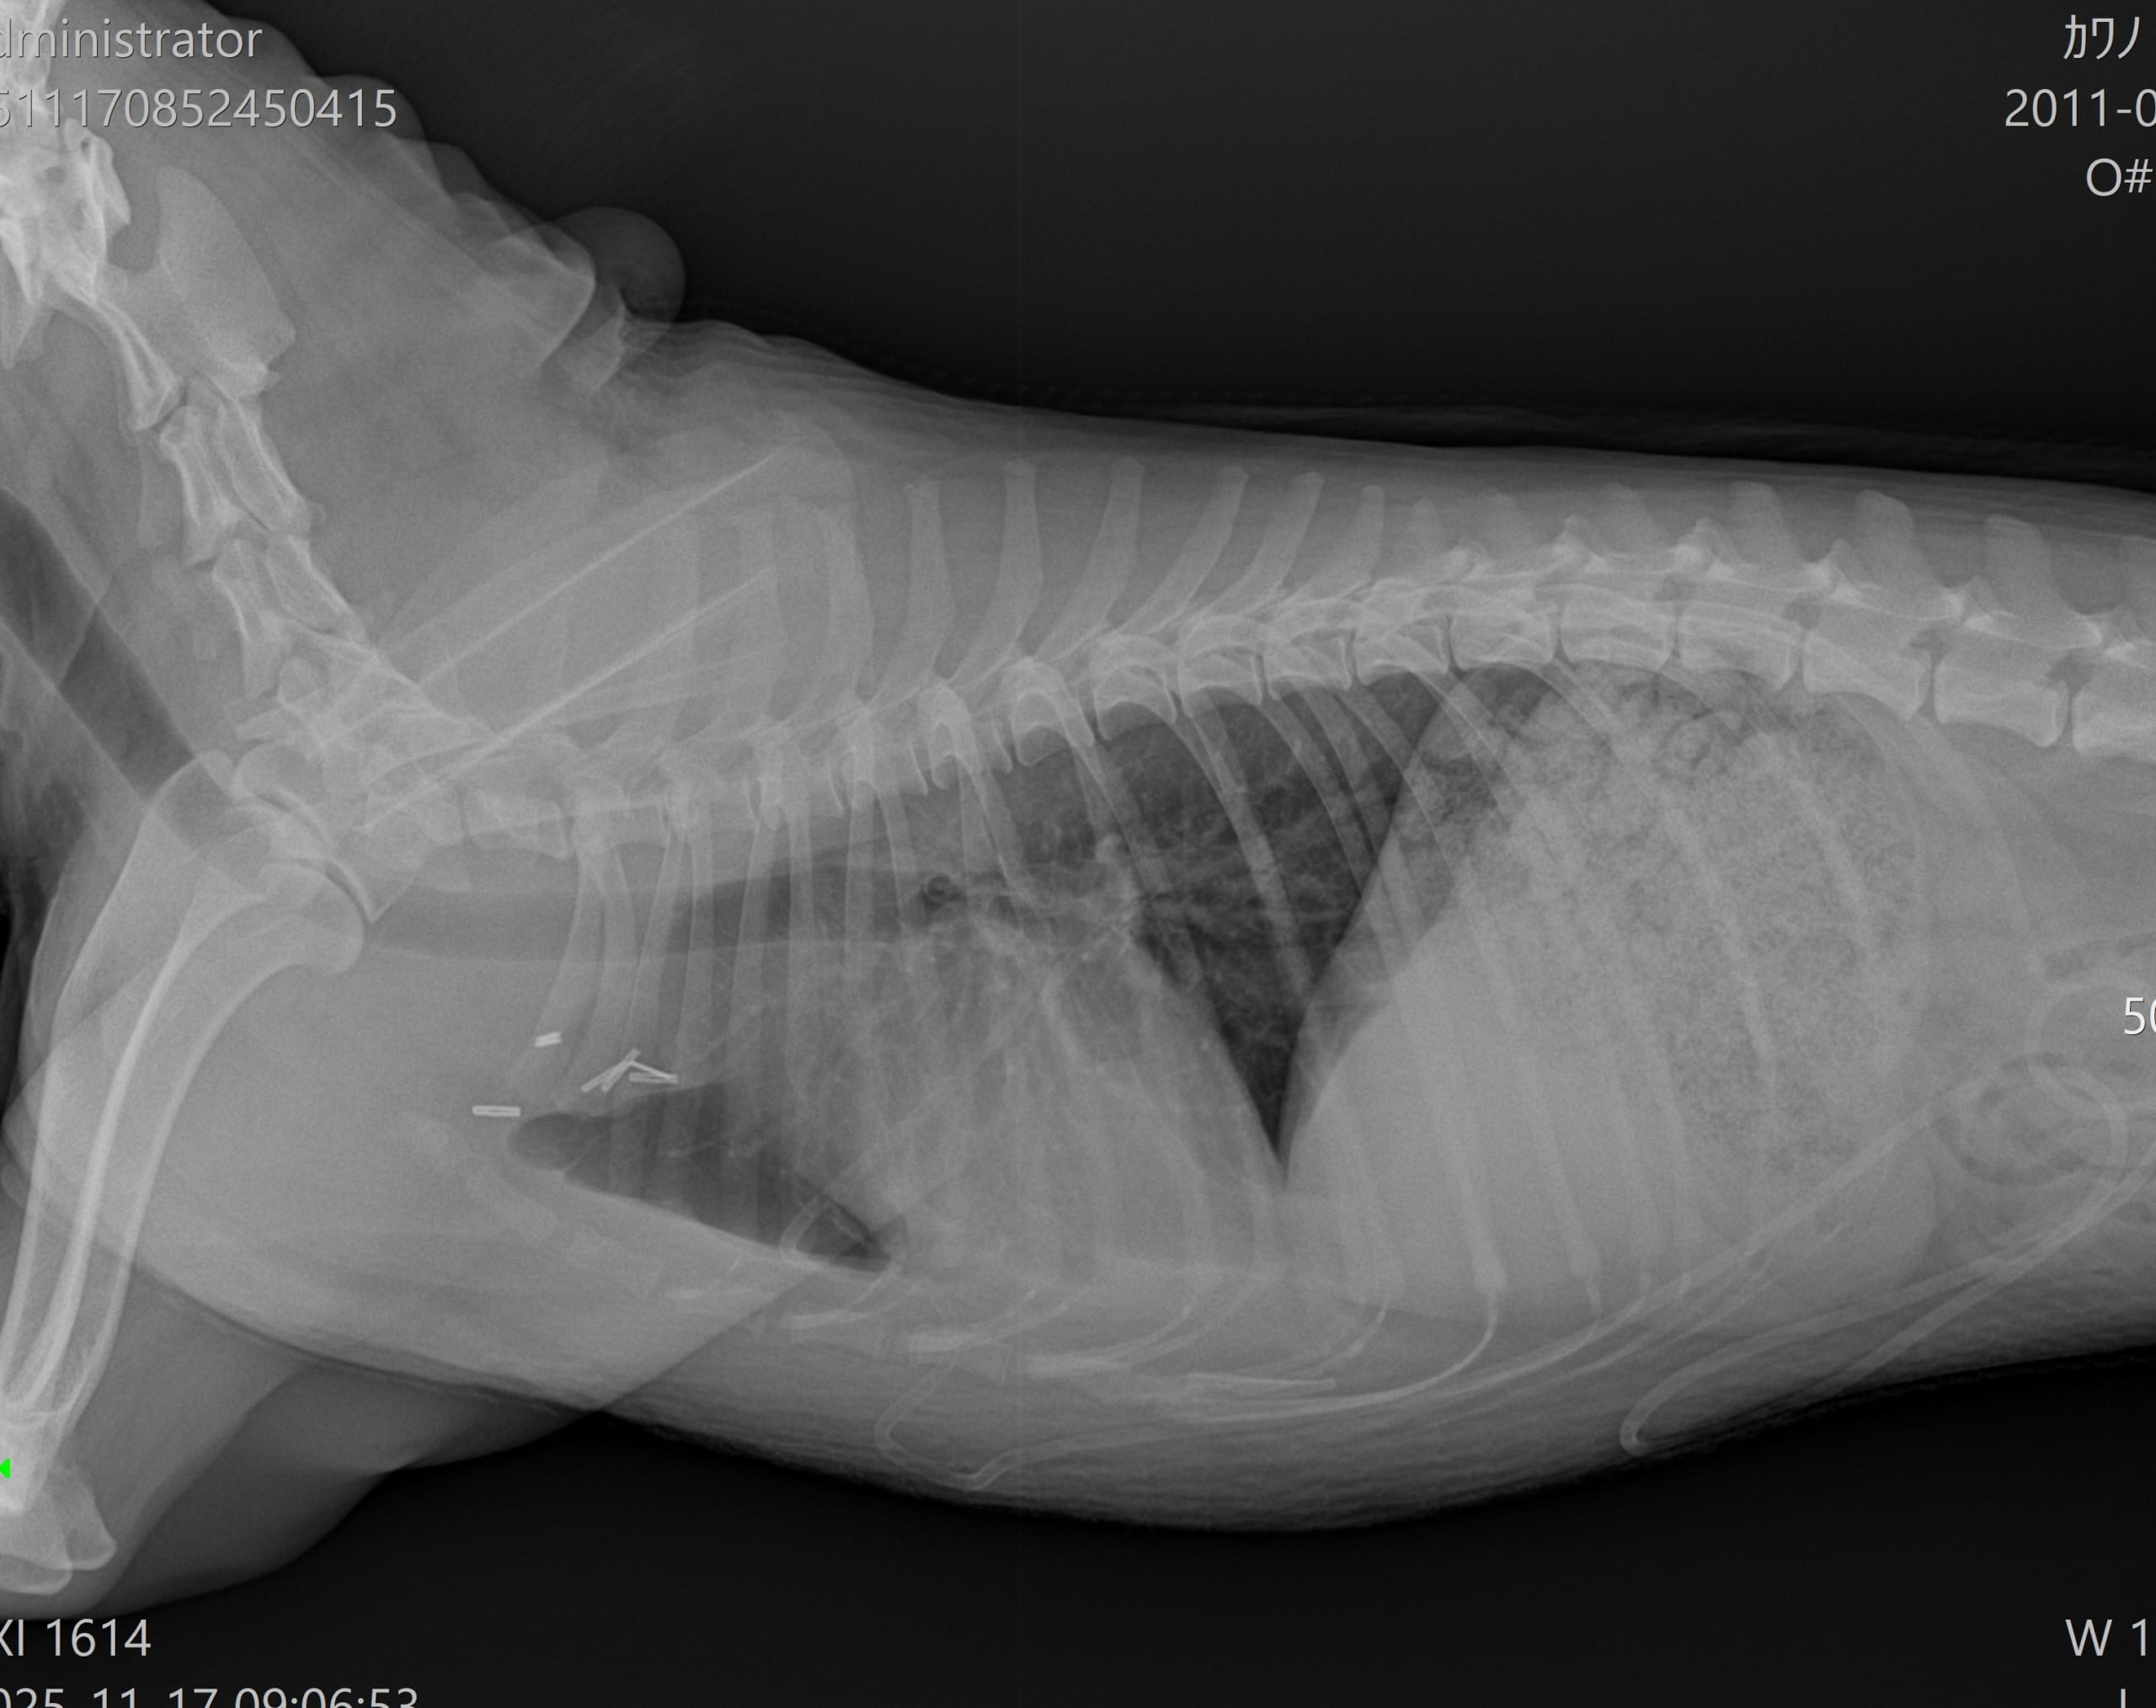

胸部レントゲン検査(腫瘤を赤丸で表示)

より詳しい評価が必要と判断し、沼津市の宮田動物病院にてCT検査をお願いしました。迅速に対応していただき、すぐにCT撮影を行っていただきました。

画像中の黒矢印で示した黄色の部分が、前胸部に認められた腫瘤です。